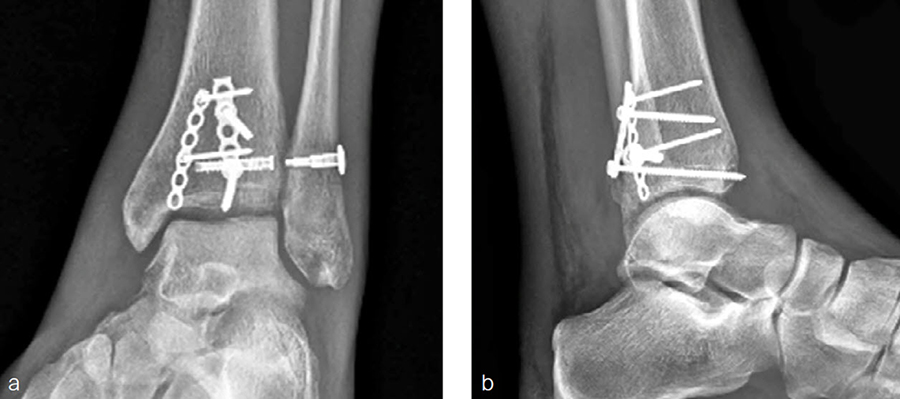

A 27-year-old man fell from a ladder sustaining a proximal fibula fracture (Fig 1) with a multipart posterior malleolar fracture (Fig 2). The patient was treated operatively with direct reduction and plate fixation of the posterior malleolar components. Intraoperative testing demonstrated continued syndesmotic instability requiring fixation (Fig 3). The syndesmosis was reduced in direct fashion and stabilized with a provisional K-wire and clamp before insertion of a FIBULINK Implant (Fig 4).

The patient healed (Fig 5) and returned to preoperative function.